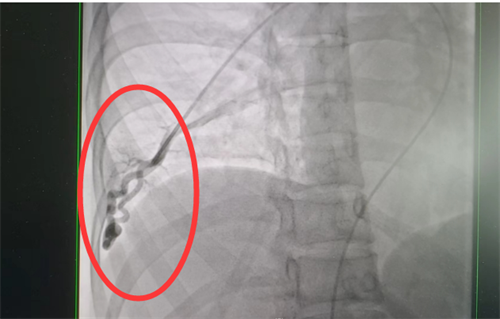

目前治疗肺动静脉瘘的方法有两种—介入手术及外科切除,可根据患者具体情况选择合适干预方式。通过积极处理,梁瑶脑梗症状得到控制,随后转入我院外周血管介入科进行介入手术治疗。此类手术难度大,风险高,经科室团队仔细讨论,定下最佳方案,为患者顺利实施了肺动静脉瘘封堵术,手术全程4小时,术后平稳回到病房。术后复查肺动静脉瘘已消失不见,经过后续的对症治疗和护理,梁瑶恢复良好,于5月上旬出院。

术前肺动静脉瘘造影